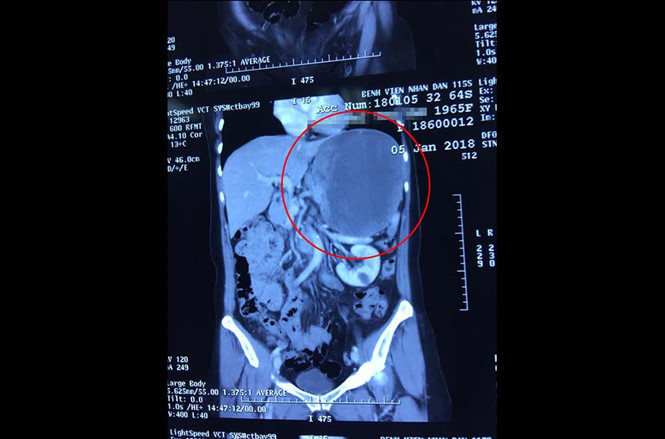

Hình ảnh khối u qua chụp CT scanner |